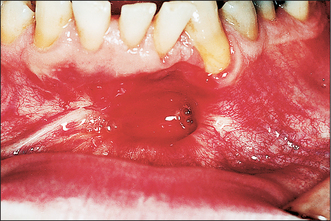

Swelling

Swelling is a common presenting complaint and if extensive can cause both intraoral and extraoral asymmetry. Importantly the swelling is normally clinically discrete and well demarcated. Where there has been extensive expansion of the cyst the overlying bone will be thin or absent. In the former, the surface will feel firm but flexible, but if the overlying bone has been completely eroded it will appear as a tense bluish swelling that feels ‘fluctuant’ (Fig. 9.4) (see Ch. 7 for a description of fluctuance).

Fig. 9.4 Bluish swelling associated with an eruption cyst on a lower first molar.